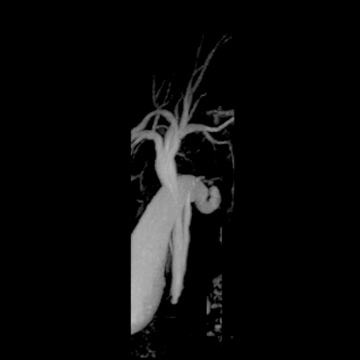

頭部MRA

matrix 320, FOV 220 mm- 頭部MRA